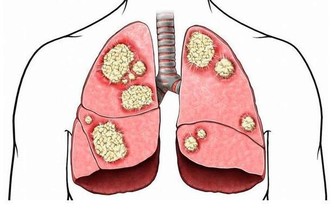

風濕疾病的患者,平時要注意盡量不要吃海產品,應該要多吃綠色的蔬菜水果,並且要適當攝入鈣元素,可以有效避免骨質疏鬆,平時也需要加強鍛煉,適當鍛煉身體,可以增強骨骼的堅硬度,可以避免骨質疏鬆,而且可以有效緩解關節疼痛,風濕病的四大飲食禁忌。

一、早期不在乎,認為自己會好。有的人早期只有一個手指、足趾或腰、背、髖關節疼痛,但卻不在乎,等到病重了才去醫院,結果容易失去最佳治療時機。